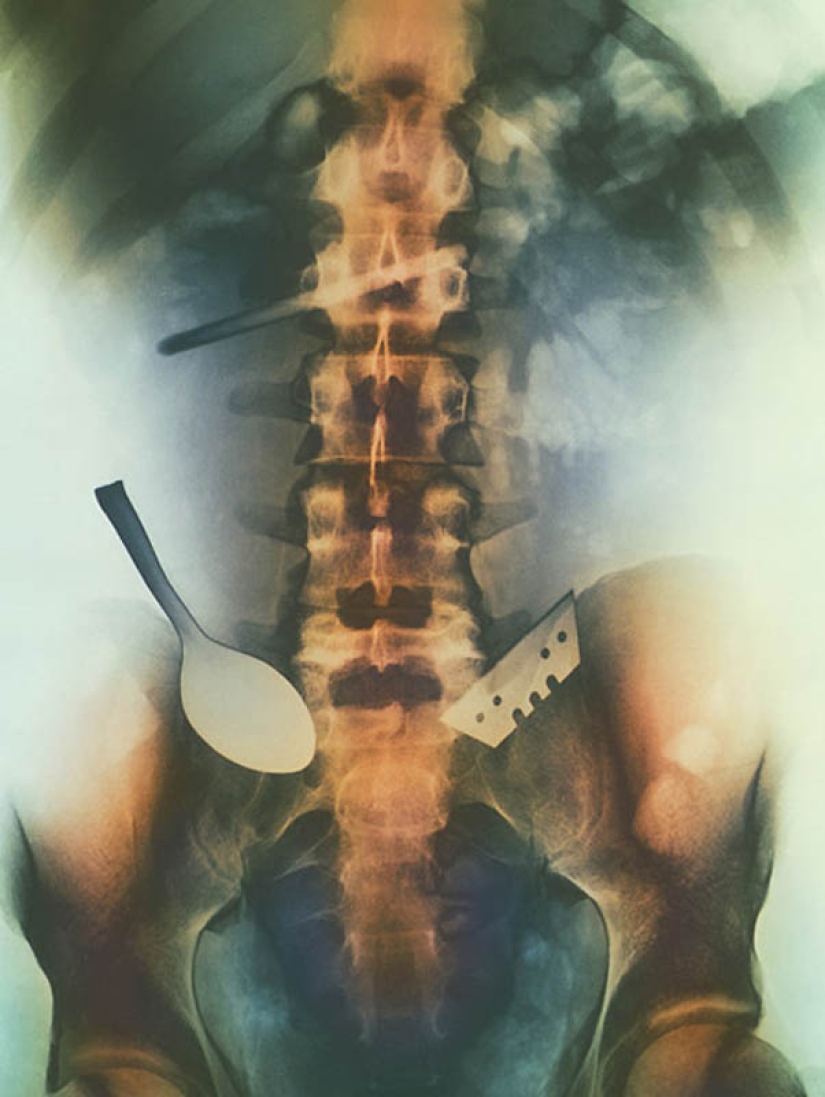

5. Imagen en color de objetos que el paciente ha tragado y que están atascados en sus intestinos, incluyendo una cuchara y una cuchilla.